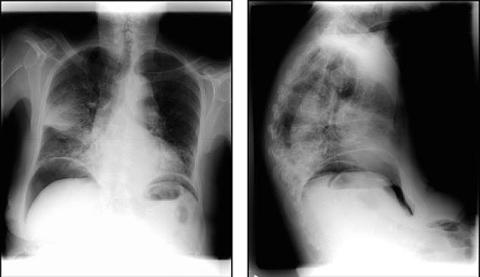

En 86-årig kvinde blev indlagt pga. et døgn varende smerter i nakken, thorax og diffust i abdomen. Hun havde i øvrigt ingen symptomer (Fig. 1).

Klinisk var patienten smertepåvirket, let febril (med en temperatur på 37,8º C) og med stetoskopisk udtalt krepitation på hø. bag- og sideflade. Abdomen var øm, blød, meteoristisk og med normale tarmlyde. Biokemisk fandtes et leukocyttal på 17 mio./l og CRP på 400 mg/l (normalområde <10 mg/l). Røntgen af thorax viste som ventet et stort højresidigt infiltrat, men desuden en anden akut behandlingskrævende tilstand: luft under begge diafragmakupler. Patienten blev samme dag opereret for perforeret ulcus ventriculi.